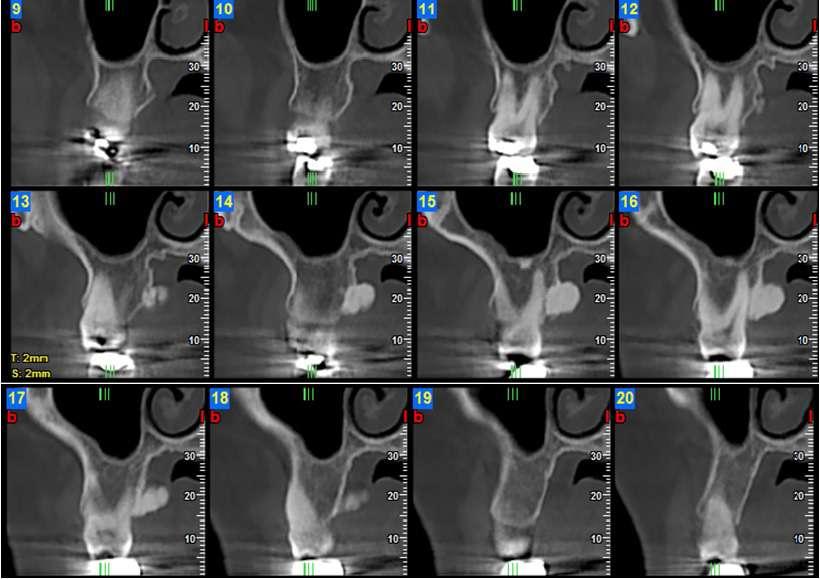

12.00 L’in uenza del genere nell’espansione scheletrica del palato, valutazione CBCT dello stadio di ossi cazione della sutura palatina mediana

Federica Altieri, Martina Mezio, Michele Cassetta